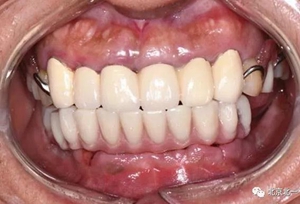

圖十九:永久修復(fù)完成

圖二十:永久修復(fù)咬合關(guān)系

圖二十五:口內(nèi)照。